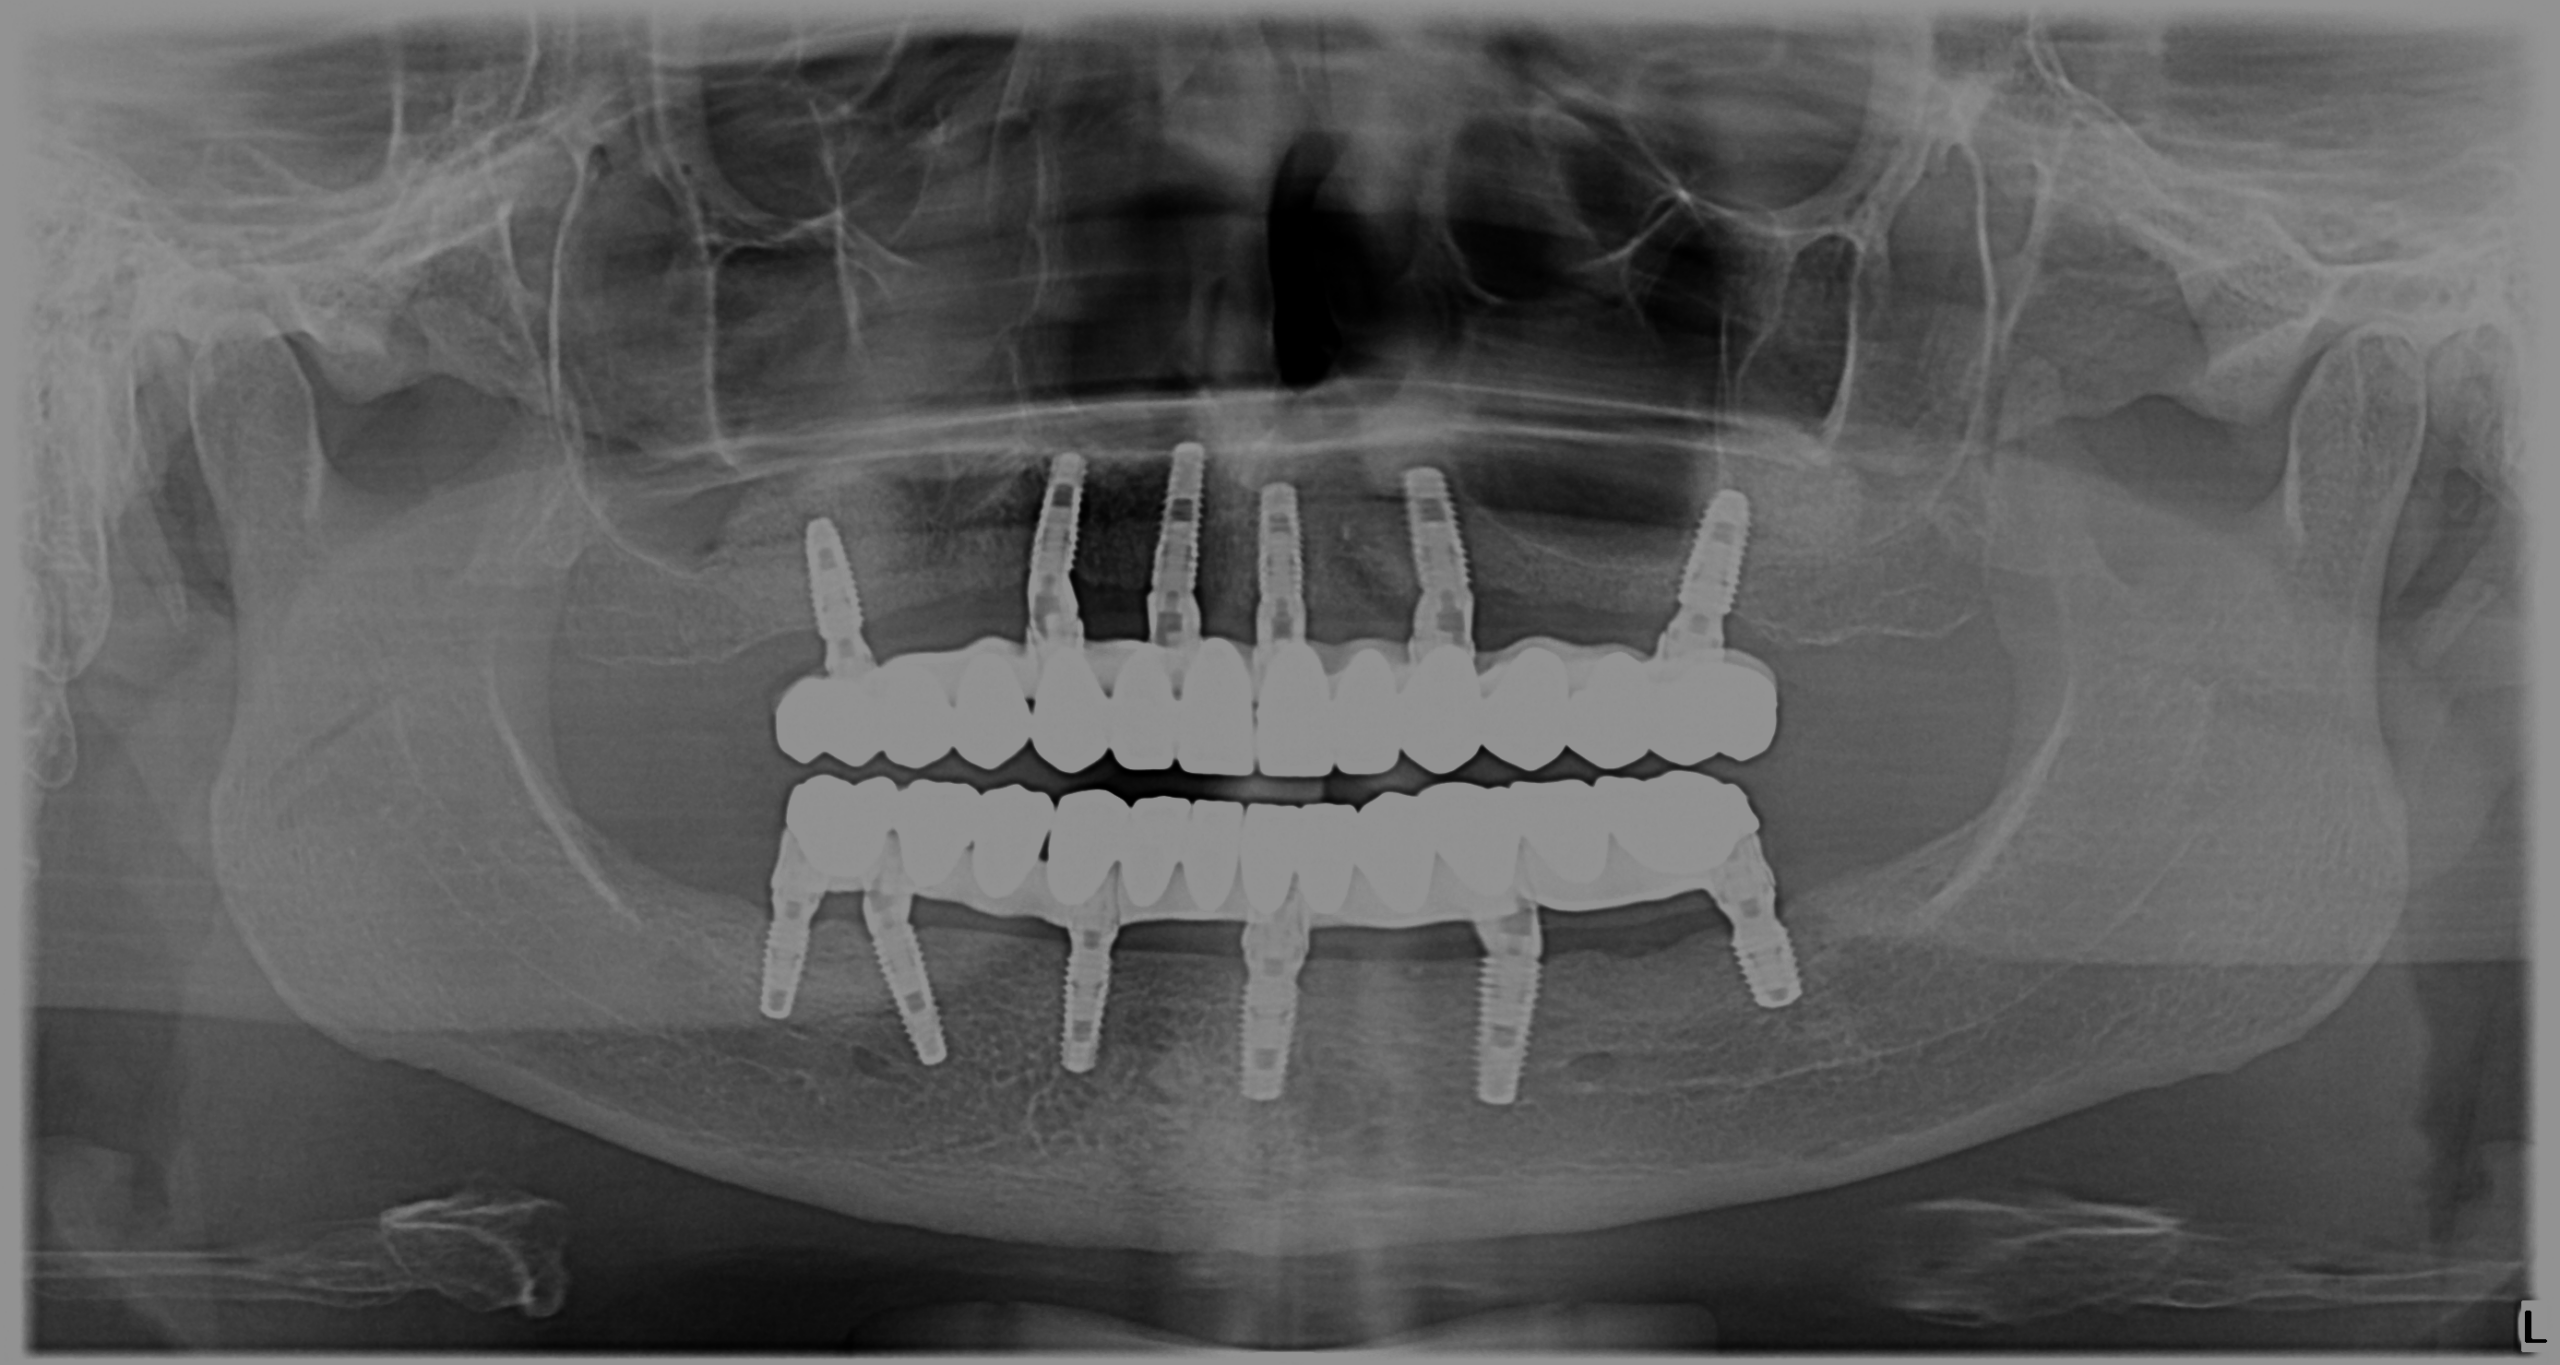

În radiografia de mai sus putem observa poziția implanturilor inserate și lucrările finale fixate la 6 luni de la intervenție. După efectuarea unor probe și amprente, am decis împreună aspectul dinților finali. Astfel, pacienta noastră este mulțumită și zâmbește cu încredere.